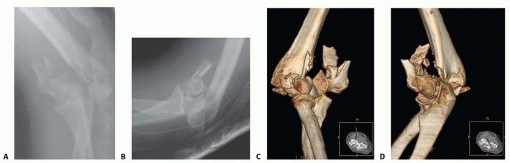

Open Reduction and Internal Fixation of Supracondylar and Intercondylar Fractures